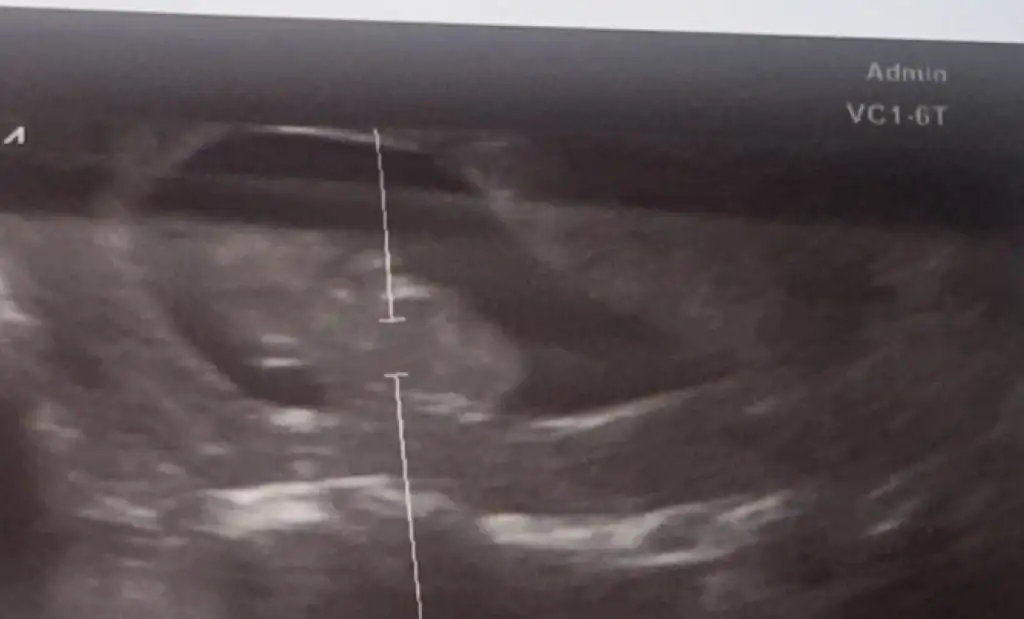

İyi akşamlar cinsiyet tahmini hiç anlamam anlayan arkadaşlar yorum yapabilir misiniz 12+2 haftalık olduk

Bizim ultrason resimleri bulanık çıkıyor nedense belli oluyor mu bende sorayım

Günaydın kızlar bugün doktor kontrolümüz vardı 11+5 dik usg de 12+2 çıktı. ikili tarama için kan verdik ense kalınlığıda 1 çıktı haftaya sonuç için gidicez. cinsiyet için doktorumla kız diye totem yaptık ama daha net olması için haftaya bakıcam dediHerşey yolunda daha şimdiden kıpır kıpır bacaklar hiç durmadığı için çok net görüntü çıkmadı ama cinsiyet tahminleriniz için ekliyorum